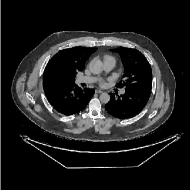

This section compares the reconstruction quality and runtime among the proposed MBIR method, PWLS-ST-, and other three MBIR methods, PWLS-EP, PWLS-DL, and PWLS-ST-. Table I shows that, for both 2D and 3D sparse-view CT reconstructions of the XCAT phantom, the proposed PWLS-ST- model outperforms PWLS-EP and PWLS-ST- in terms of RMSE. In addition, PWLS-ST- using a square transform (of size ) achieves lower RMSE than PWLS-DL using an overcomplete dictionary (of size ) for 2D sparse-view reconstructions. Fig. 3(a) and Fig. 4 show the reconstructed images for 2D and 3D phantom experiments, with different reconstruction models and different number of views. (See the corresponding error maps in the supplement.) The proposed PWLS-ST- consistently gives more accurate image reconstructions compared to other MBIR methods. Specifically, PWLS-ST- has smaller errors in the heart region (see zoom-ins in Fig. 3(a)) of 2D reconstructions than PWLS-DL and PWLS-ST-. In addition, compared to PWLS-ST-, PWLS-DL and PWLS-ST- have some ringing artifacts around the edges with high transition, e.g., edges between air and soft tissues. (See a comparison of profiles of PWLS-ST- and PWLS-ST- in the supplement.) In particular, PWLS-ST- and PWLS-DL give more visible ringing artifacts for 2D reconstruction from fewer views, and PWLS-ST- has these ringing artifacts for 3D reconstructions regardless of the number of views (see zoom-ins in Fig. 4). Table II reports runtimes of different MBIR methods in reconstructing the -views XCAT phantom scan. (FBPConvNet is a non-MBIR method and its runtime for processing a image is approximately one second with a TITAN Xp GPU.) While providing better reconstruction quality, the proposed Algorithm 1 of PWLS-ST- has shorter runtime compared to the algorithms of PWLS-DL and PWLS-ST- in Section III-A. Similar to the PWLS-EP algorithm, the reconstruction time of the PWLS-DL, PWLS-ST-, and PWLS-ST- algorithms can be further reduced by using ordered subsets [51].

![]() |

| (b) 3D axial cone-beam CT experiments |